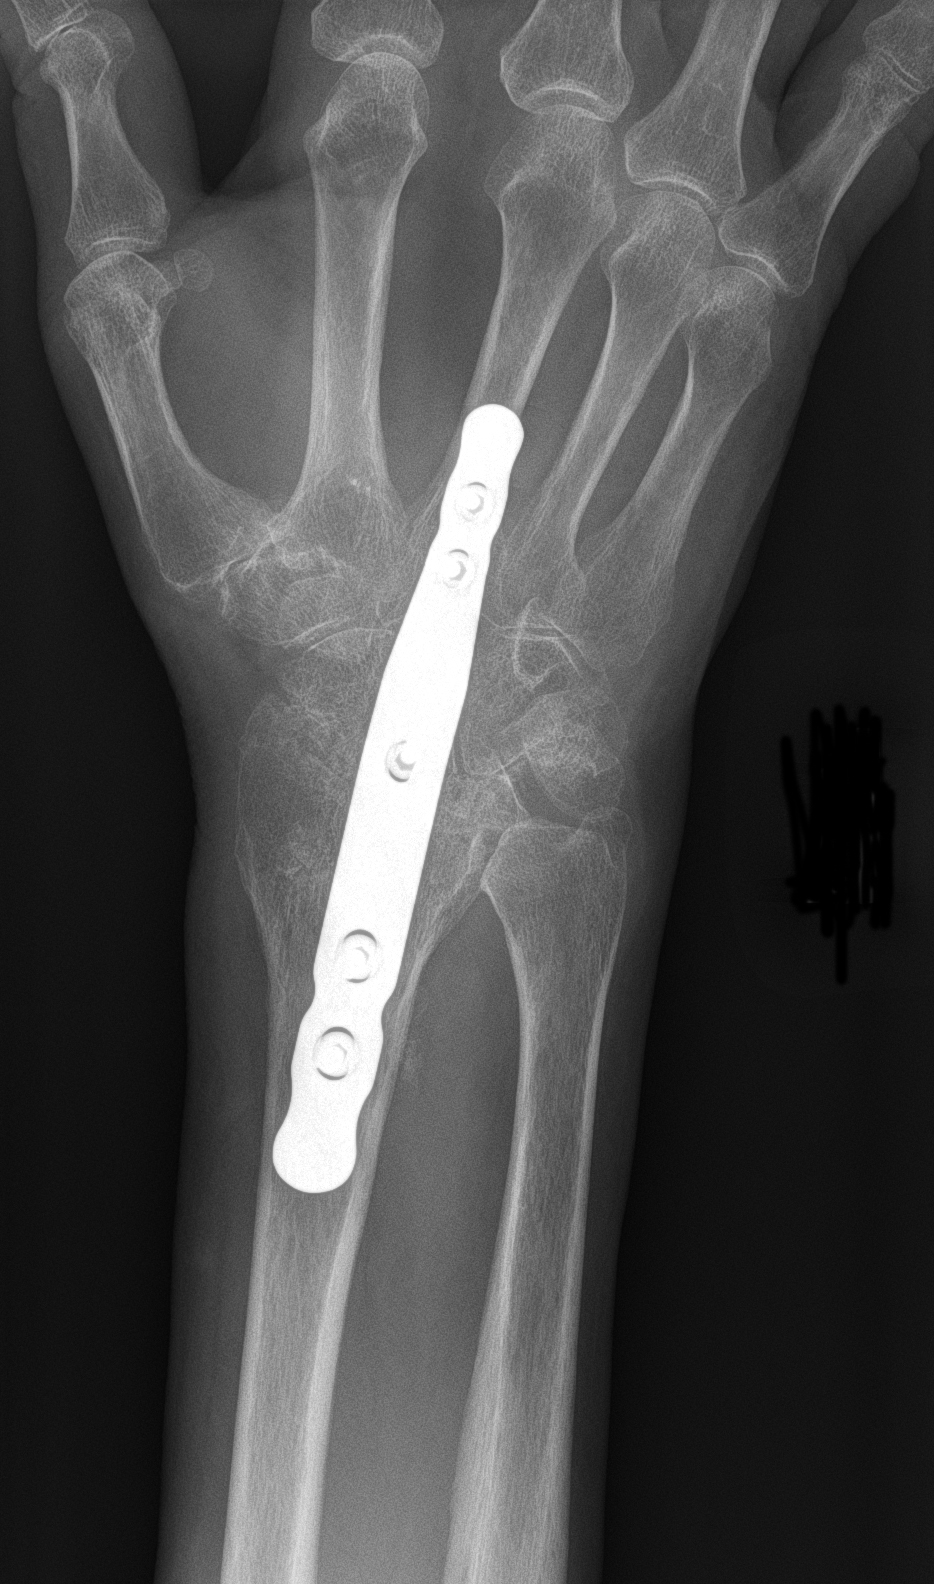

Popular topics On the part of the bodyFeaturedPatellofemoral Pain syndrome Broken neck fracture (broken collar)Public themes by the body Knee ArthroscopyTotal Hip ReplacementPopular Thematics By Part of the Body Activities After Kneeator Cuff and Shoulder Conditioning ProgramPopular Themes By BodyFeoneturedA Safety Guide Your best health. Diseases " Highlights Treatment of Popular Themes Popular Theme Recovery Popular Themes Maintain HealthyFeaturesPopulers PrintEmailFacebookTwitterKienböck's DiseaseKenböck's disease is a condition where the blood supply is interrupted to one of the small bones of the wrist, the lunatic. The bone is living tissue that requires a regular supply of blood to nourish. If the blood supply to a bone stops, the bone can die. This is called osteonecrosis. The damage to the lunatic causes a painful and rigid wrist and, over time, can lead to arthritis. Because the cause of Kienböck's disease is not known. Many people with Kienböck's disease think they have a sprained wrist at first. They may have experienced some form of wrist trauma, like a fall. This type of trauma can interrupt blood flow to the lunatic. Some things may put you at greater risk for the disease. For example, most people have two glasses that supply blood to the lunatic, but in some people there is only one source. This can delay blood flow to the bone. Also, if the two bones of the forearm (the radio and ulna) are different lengths, you can press extra to the lunatic during some wrist movements. Over time, this extra stress on the bone can lead to Kienböck disease. SymptomsThe most common symptoms of Kienböck's disease include: Medical Exam Kienböck's disease is a condition that progresses slowly, and many people don't decide to see a doctor until they have experienced symptoms for several months, perhaps more. During your first appointment, your doctor will discuss your symptoms and medical history, and then examine your hand and wrist. In its early stages, Kienböck disease may be difficult for your doctor to diagnose because the symptoms are so similar to those of a sprained wrist. Imaging tests, such as X-rays and MRI images, are used to confirm a diagnosis of Kienböck disease. Kienböck disease progresses through four stages of gravity. If you are diagnosed with Kienböck disease, your doctor will plan your treatment based on several factors, which is more important, the stage of your progression. Stage 1During the first stage of the disease, the symptoms are similar to those of a wrist sprain. Although the blood supply to the lunatic has been interrupted, X-rays may appear normal or suggest a possible fracture. An MRI analysis can better detect blood flow and is useful for making diagnosis at this early stage. Stage 2The lunar bone begins to harden due to lack of blood supply during Stage 2. This hardening process is called sclerosis. In addition, the lunatic will appear brighter or whiter in X-ray areas, indicating that the bone is dying. To better assess the condition of the lunatic, your doctor may also order MRI scanners or CT scans. The most common symptoms during this stage are wrist pain, inflammation and sensitivity. Stage 3In the third stage, the dead lunar bone begins to collapse and break into pieces. As the bone begins to break, the surrounding bones can begin to change the position. During this stage, patients often experience growing pain, weakness in grip and limited wrist movement. Stage 4If the condition progresses to Stage 4, the surfaces of the bones surrounding the lunatic also deteriorate, and the wrist can become arthritic. Treatment Although there is no complete cure for Kienböck disease, there are several non-surgical and surgical options to treat it. Treatment goals are to relieve pressure on the lunatic and try to restore blood flow inside the bone. Related Articles Wrist Arthritis Wrist Sprains Non-surgical Treatment In the very early stage of the disease, pain and inflammation can be given with anti-inflammatory drugs, such as aspirin or ibuprofen. Doll immobilization for a period of time can help relieve pressure on the lunatic, and your doctor may recommend spine or casting for 2 to 3 weeks. It is important to monitor any changes in your symptoms during the early stage of Kienböck disease. If the pain is not relieved with simple treatments or returns, the doctor may recommend surgery. Surgical Treatment There are several surgical options to treat Kienböck disease. The choice of the procedure will depend on several factors, in particular to what extent the disease has progressed. Additional factors to consider are the patient's level of activity, personal objectives and the surgeon's experience with the procedures. Revascularization. In some cases, it may be possible to return the blood supply to the lunar bone. This procedure is called revascularization. It is more successful during the early stages of the disease—stages 1 and 2—before the lunatic has deteriorated significantly. Revascularization involves the removal of a portion of bone with attached blood vessels from another bone — most of the time a bone from the forearm (radius) or an adjacent bone in the hand. This piece of bone with its blood supply is called vascularized graft. It is inserted into the lunar bone. To help the bones remain in place during healing, an external fixer can be temporarily applied. This is a metallic device attached to the outside of the wrist with nails inserted into the bones. It can relieve pressure on the lunatic while the graft is healing and restoring a blood supply. Joint leveling. If the two bones of the lower arm are not of the same length, a joint leveling procedure may be recommended. Bones can be made longer using bone grafts or shortened by removing a section of the bone. This leveling procedure reduces the forces that compress the lunatic and often stops the progression of the disease. Approximate line spectomy. If the lunatic collapses severely or breaks into pieces, it can be eliminated. In this procedure, the two bones on each side of the lunatic are also eliminated. This procedure, called proximal row carpectomy, will relieve pain while maintaining partial wrist movement. (Left) The three wrist bones that are removed in a proximal row carpectomy are shaded here. (Right) An X-ray image of a wrist after a proximal row carpectomy. Fusion. To relieve pressure on the lunatic, the nearby bones of the wrist can be merged together to make a solid bone. A fusion can be partial, in which only some of the bones are merged. This procedure relieves pain and retains some wrist movement. If the disease has progressed to severe wrist arthritis, fusing all wrist bones to the radio will relieve pain and improve the hand function. Although the whole wrist movement is eliminated in a complete fusion, the rotation of the forearm is preserved. In a fusion, the bones of the wrist are held along with a plate, screws and pins. ResultsThe disease of Kienböck varies considerably in its severity, as well as its rate of progression. Each patient's response to treatment depends on the degree of damage to the bones of the lunar and surrounding wrist. Some patients may require more than one procedure if the disease continues to progress. In short, patients with Kienböck disease should not expect to return to normal wrist function after any treatment. However, treatment provides the greatest opportunity for long-term preservation of function and pain relief. Last revision May 2012 Contributed Updated byPeer-Reviewed byAAOS does not support any treatment, procedures, products or doctors referred here. This information is provided as an educational service and is not intended to provide medical advice. Anyone looking for specific orthopedic advice or assistance should consult your orthopedic surgeon, or locate one in your area through the AAOS program on this website. Copyright ©1995-2021 by the American Academy of Orthopaedic Surgeons. All material on this website is protected by copyright. All rights reserved. This website also contains copyrighted material by third parties.